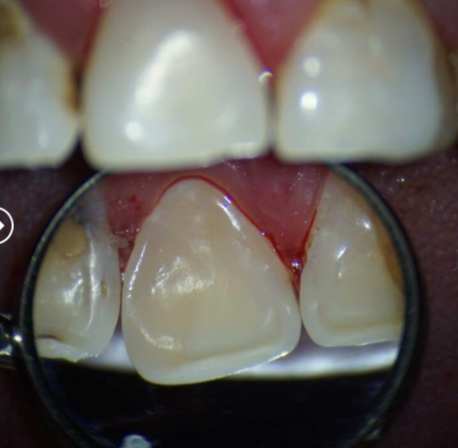

Сокольская Оксана Юрьевна: портфолио (2)